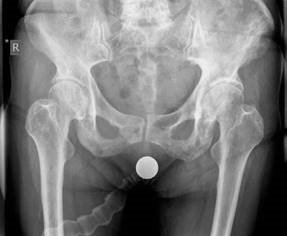

Hip structured oral questions Structured Hip oral examination question 1 EXAMINER : This is a radiograph of a…